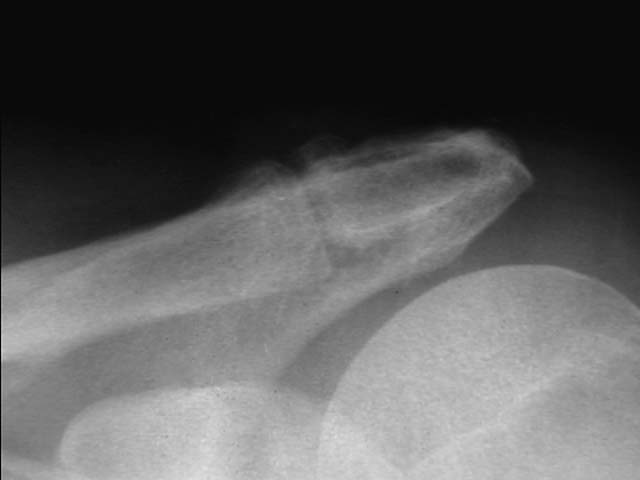

To provide an opportunity for the comparison of image scanning techniques, we are posting in the "Digital Images" forum of the HWB Home Page (http://www.hwbf.org/hwb/) an AP Shoulder film scanned with a $16,000 Howtek Scanmaster DX Xray scanner and a $200 "Snappy" video digitizer. The "Snappy" plugs into the video port of a camcorder or VCR. JPEG compression of either 5:1 or 10:1 are applied to the scans. We would be interested in any feedback with respect to the diagnostic quality of these images.

Click images to enlarge.ROW 1: JPEG 5:1 compression

1)